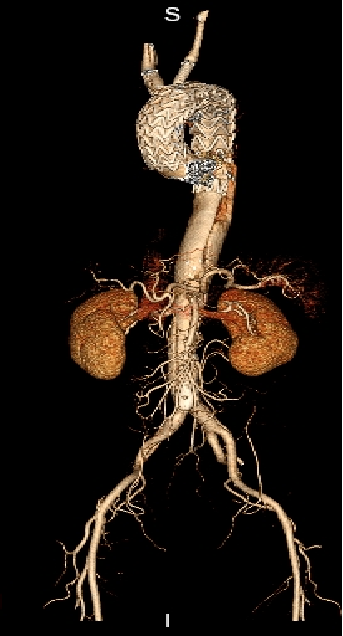

男性,44岁,慢性B型夹层。2010年12月行TEVAR术。

2013年5月发现RTAD,未处理。2015年2月死亡。

▎病例二

男,52岁,慢性夹层。2015年8月入院,4年前曾因B型层行TEVAR术,主动脉解剖变异,扭曲。行双烟囱+TEVAR术。术后第3天RTAD ,死亡。

▎病例三

男,60岁,慢性夹层。2013年12月行Debranching+TEVAR术 。2016年7月复查: RTAD ,未手术。失访。

▎病例四

男, 49岁,急性夹层 。2018年11月TEVAR。一月后复查:RTAD 。 2019年1月双开窗。2019年4月2日 复查,结果良好。